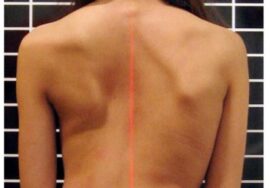

عند محاولة تصحيح اعوجاج العمود الفقري، يجب التغلب على جميع القوى المقاومة للانحناء. بعض المقاومة تأتي من الأربطة القصيرة والمتشددة والعظام غير المتماثلة، وهذه يمكن تعديلها أو قصها أثناء الجراحة. لكن هناك قوة واحدة لا يمكن تعديلها: الحبل الشوكي.

الحبل الشوكي يمتد داخل قناة العمود الفقري، وعند محاولة جعل العمود الفقري مستقيمًا، يُصبح طول القناة أكبر، مما يؤدي إلى شد الحبل الشوكي. إذا حاول الجراح جعل العمود الفقري مستقيمًا بالكامل، فإن شد الحبل الشوكي قد يؤدي إلى شلل دائم عند بعض الأطفال.

يتفق معظم الجراحين على أن الحبل الشوكي يكون قصيرًا أو متوترًا عند العديد من حالات الاعوجاج الطفولي غير معروف السبب، والذي يُعرف باسم اعوجاج العمود الفقري مجهول السبب. ما يزال هناك جدل حول مدى تأثير هذا الشد على تطور الانحناء.

منذ عام 1968، ظهرت فرضية تقول إن الحبل الشوكي الضيق قد يكون السبب الرئيسي لمعظم حالات الاعوجاج الطفولي غير معروف السبب. عندما يُتجاهل شد الحبل الشوكي، يشبه الأمر ترك حريق الغابة يشتعل بلا سيطرة، مما يؤدي إلى تفاقم الاعوجاج أثناء نمو الطفل ومرحلة البلوغ.